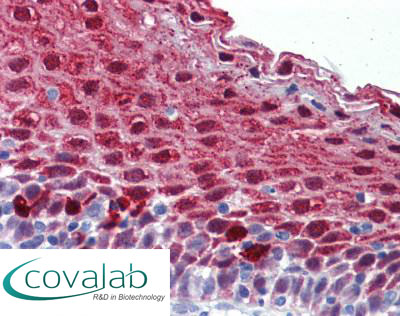

Anti-MARK3 antibody IHC staining of formalin-fixed, paraffin-embedded human tonsil after heat-induced antigen retrieval.